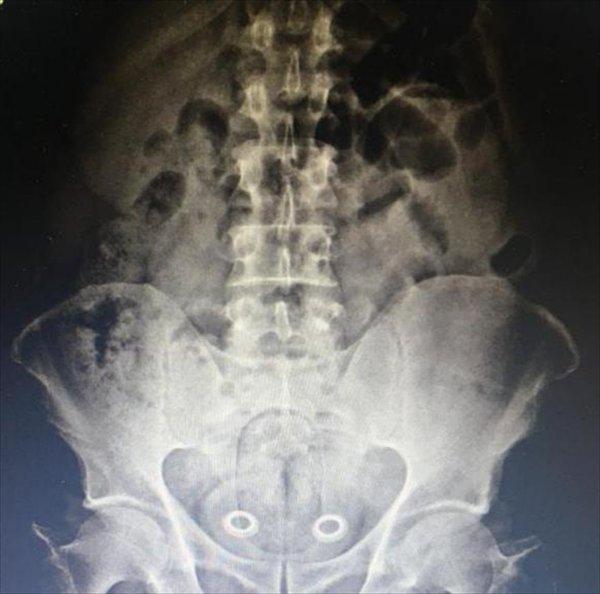

MİDE VE BAĞIRSAKLARINDAN ÇIKTI

Burada çekilen röntgen sonucu İran uyruklu A.P.'nin mide ve bağırsaklarında kapsüller içerisinde 107.92 gram metafetemin, folyoya sarılı 3 gram metamfetamin, 64 gram esrar tespit edildi. Gözaltına alınan İran uyruklu A.P. ile beraberindeki N.Ş., Ö.A., M.Y., Ş.K.'nin emniyetteki işlemleri sürüyor.